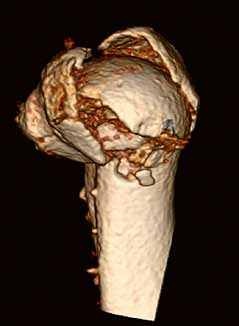

Die Klinik verfügt über 14 Computertomographen (CT), zwölf Magnetresonanztomographen (MRT) sowie zahlreiche Ultraschallgeräte. Allein am Campus Benjamin Franklin führen die Radiologen an sieben Tagen die Woche je zwischen 50 und 60 CT Untersuchungen täglich durch. Seit knapp drei Monaten steht ihnen dazu der neue 160-Schicht-Low-Dose-CT Aquilion PRIME zur Verfügung. Ein weiterer Aquilion PRIME sowie ein 640-Schicht-Volumen-CT Aquilion ONE ViSION EDITION wurden am Campus Mitte installiert. „Als wir nach einem neuen CT gesucht haben, war klar, dass dessen Ausstattung allen universitären diagnostischen Anforderungen gerecht werden muss", erklärt Dr. Stefan Niehues, Radiologe und Oberarzt der Klinik für Radiologie am Campus Benjamin Franklin.

„Mit dem neuen CT Aquilion PRIME können wir das komplette radiologische Spektrum der Charité abdecken. „Die gesamte Polytrauma-Diagnostik über die Akutversorgung bis hin zur Neuroradiologie und Diagnostik bei jungen Menschen führen wir mit dem Aquilion PRIME durch."

Dass sich Dr. Niehues und sein Team in einem langen und aufwendigen Entscheidungsprozess für das innovative CT aus dem Hause Toshiba ausgesprochen haben, hat mehrere Gründe. „Ich war Sofort beeindruckt von der Rechnergeschwindigkeit", sagt Dr. Niehues. Die Rekonstruktion der Bilder erfolge am Aquilion PRIME in einem Bruchteil der Zeit, die früher vergangen sei, bis das CT die komplette Bildserie samt Rekonstruktionen erstellte. „Heute haben wir alle Bilder nach wenigen Minuten", weiß Dr. Niehues, er hat das Intervall zwischen Untersuchung, Scan und Rekonstruktion aus Interesse selbst gestoppt. Früher sei das Polytrauma-Team samt Patient dann oft schon längst wieder verschwunden gewesen. „Die ständige Entscheidung zwischen schneller Rekonstruktion und einer kompletten Serie in dünnen Schichten und guter Bildqualität fand ich belastend - mit dem Aquilion PRIME hat sich das Problem gelöst", resümiert Dr. Niehues.

Neben der Rechnergeschwindigkeit lautet das Schlüsselwort bei dem neuen Gerät „Adaptive Iterative Dosis-Reduktion (AIDR 3D)". „Dieser mathematische Algorithmus erlaubt es uns, mit einem Bruchteil der Dosis zu arbeiten, die wir bisher für die erforderliche Bildqualität benötigt haben", weiß der Radiologe.

„Durch die Spitzentechnologie können wir bei gleich hoher Bildqualität die Dosis an Röntgenstrahlung bei vielen Untersuchungen auf ein Drittel reduzieren."

Darüber hinaus bietet der Aquilion PRIME neue Untersuchungsmöglichkeiten, wie die Body-Perfusion und Dual-Energy, die bald eingesetzt werden sollen.